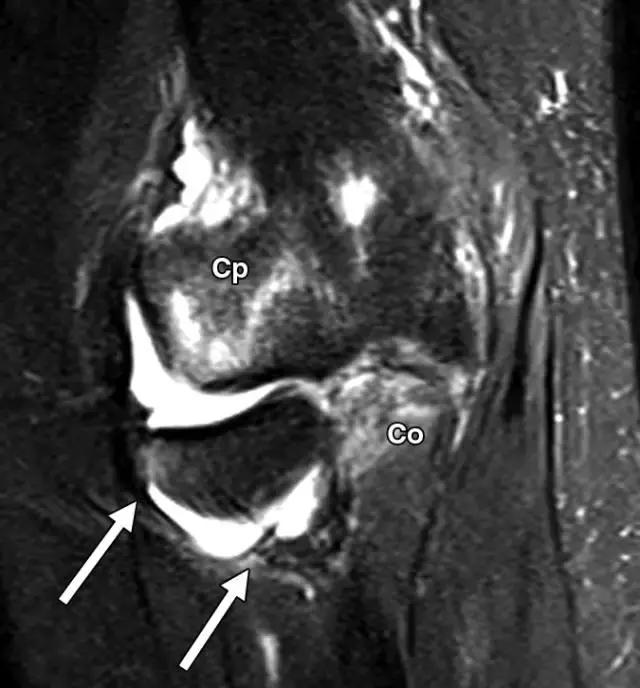

反向Segond骨折,是内侧胫骨平台的撕脱骨折,它是后交叉韧带严重受损的标志。这种骨折中的放射学检查结果与经典Segond骨折相似,只是反向骨折涉及胫骨近端的内侧(图6A)。据认为是由于内侧副韧带的深部荚膜组分的撕脱引起的(图6B),并且经常与内侧副韧带的严重损伤和相邻内侧半月板的周边损伤有关。

图6B,冠状脂肪抑制T2加权MR图像显示内侧胫骨平台内有明显的骨髓水肿,与内侧副韧带深部囊膜组分相关的反向Segond撕脱性骨折(箭头)。